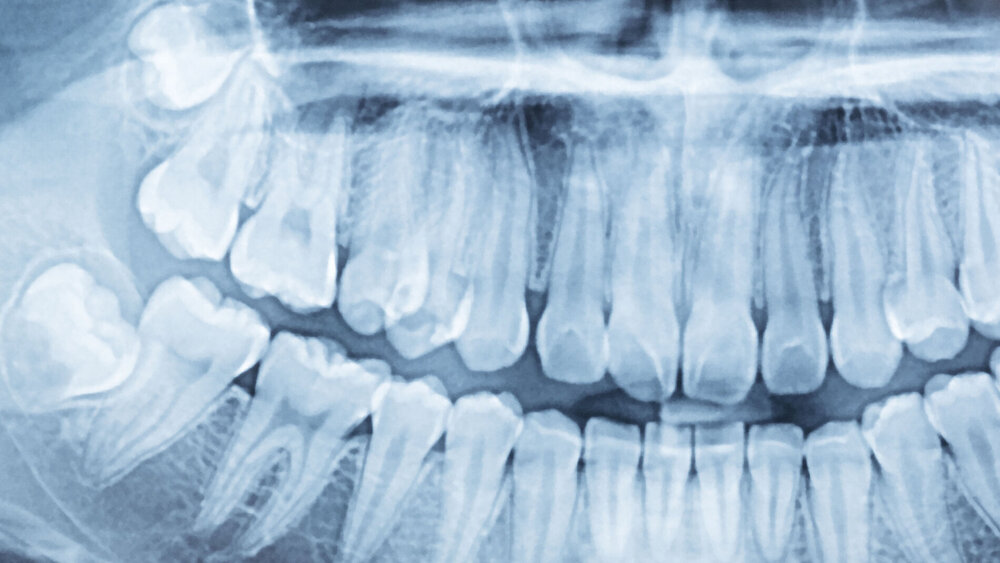

Bereits in der Leitlinie von 2013 wurde die traditionelle Unterscheidung von klinisch beziehungsweise radiologisch symptomlosen und symptomatischen Zähnen in Frage gestellt. Diese Einschätzung wird in der aktualisierten Leitlinie bekräftigt und mit Erkenntnissen aus neueren wissenschaftlichen Arbeiten unterlegt. So ist bei belassenen Weisheitszähnen nicht nur zu einem relevanten Teil mit pathologischen Veränderungen, die sich auch auf die parodontale Situation der angrenzenden Molaren und darüber hinaus auswirken können, sondern "auch an benachbarten 12 Jahr Molaren mit einer hohen Rate (bis rund 50 Prozent) an distaler Karies als Folge einer engen Lagebeziehung zum Weisheitszahn zu rechnen (McArdle et al. 2016, Kang et al. 2016)". Vor diesem Hintergrund "erscheint eine grundsätzliche Unterscheidung zwischen prophylaktischer und therapeutischer Weisheitszahnentfernung nicht mehr gerechtfertigt", so die Leitlinienautoren.

Zum Thema DVT wird als Statement formuliert: "Eine dreidimensionale Bildgebung ist vor einer Weisheitszahnentfernung nicht erforderlich, wenn in der konventionell zweidimensionalen Bildgebung keine Hinweise auf eine besondere Risikosituation vorliegen." Bislang konnte nicht gezeigt werden, "dass der Gewinn an Informationen über die Wurzelmorphologie und Topographie durch die 3-D-Diagnostik tatsächlich zu einer anderen operativen Vorgehensweise geführt hat und dass diese dann auch in einer verminderten Nerv-Schädigungsrate resultiert."

Auf der anderen Seite kann die dreidimensionale Bildgebung indiziert sein, "wenn in der konventionellen zweidimensionalen Bildgebung Hinweise auf eine unmittelbare Lagebeziehung zu Risikostrukturen oder pathologischen Veränderungen vorhanden sind und gleichzeitig aus Sicht des Behandlers weitere räumliche Informationen entweder für die Risikoaufklärung des Patienten, Eingriffsplanung oder auch für die intraoperative Orientierung erforderlich sind."